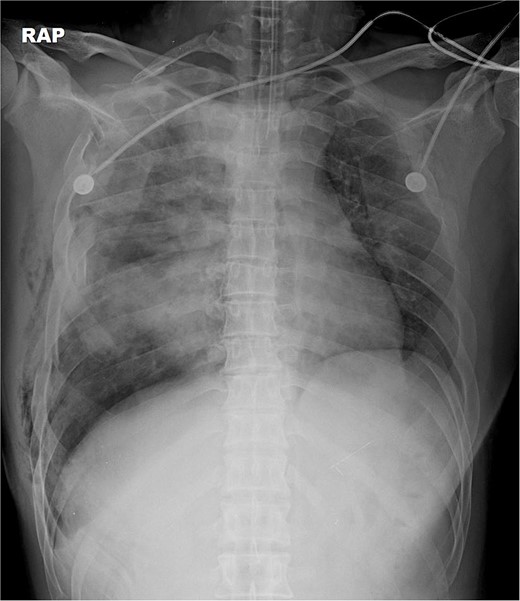

A 31-year-old unconscious male was in an unwitnessed accident when a car hit the motorcycle he was driving. A rescue team transported him to the emergency department. Clinical examination revealed hypoxia with SpO2 at 85%, tachycardia at 126 bpm, hypotension of 69/58 mmHg, and hypothermia at 35.8°C. Initial arterial blood gas analysis (ABGA), pH, PaO2, and pCO2 were 6.92, 49, and 58, respectively. Chest X-ray showed right hemopneumothorax, mediastinal shifting, and multiple bilateral rib fractures (Fig. 1). A right-side closed thoracostomy was performed. The chest drainage of 1 L was bloody. Chest computed tomography (CT) showed fractures in the right ribs 1 to 9 and left ribs 1 to 7, as well as lung contusions, multiple lung lacerations, right hemopneumothorax, and active hemorrhage in the right upper and lower lung lobes (Fig. 2). Brain and abdominopelvic CT showed no organ injury. An emergency thoracotomy was ordered.

A contrast-enhanced chest CT scan after blunt chest trauma. Chest radiograph showed right hemopneumothorax and left hydropneumothorax. Multifocal extensive hemorrhage/pneumatocele formation was visible on the right side along with combined active bleeding (arrows) in the right lung.